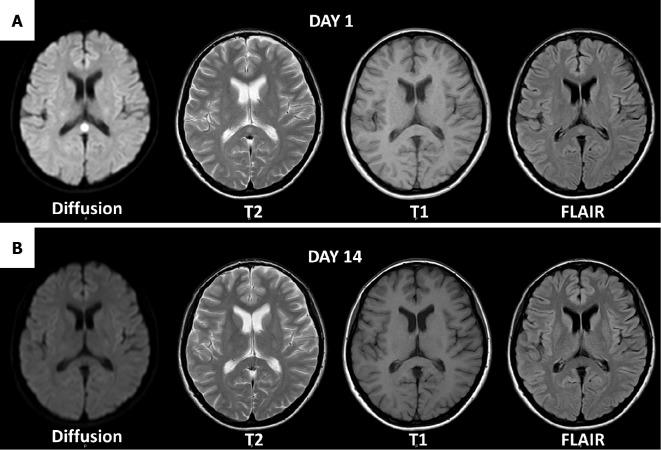

We herein report the case of a 31-year-old Japanese woman who developed adult-onset clinically mild encephalitis/encephalopathy with a reversible splenial lesion (MERS) and presented with consciousness disorder and olfactory disturbance secondary to influenza A infection. The patient's neurological symptoms and the lesion in the splenium resolved within 14 days without therapy. Magnetic resonance images and the clinical course were consistent with a diagnosis of MERS; however, mental changes following the influenza infection always present a diagnostic dilemma for physicians. We considered various diagnoses, including viral encephalitis, medication-related encephalopathy, and MERS. A comprehensive assessment may be required to diagnose MERS, since it may mimic other neurological diseases, such as viral encephalitis and medication-related encephalopathy.

摘要

我们在此报告一例31岁的日本女性病例,该患者患成人起病的临床症状较轻的伴有可逆性胼胝体压部病变的脑炎/脑病(MERS),继发于甲型流感感染后出现意识障碍和嗅觉障碍。患者的神经症状和胼胝体压部的病变在未经治疗的情况下于14天内消退。磁共振成像和临床病程与MERS的诊断相符;然而,流感感染后的精神变化总是给医生带来诊断难题。我们考虑了各种诊断,包括病毒性脑炎、药物相关性脑病和MERS。由于MERS可能模仿其他神经系统疾病,如病毒性脑炎和药物相关性脑病,因此可能需要进行全面评估以诊断MERS。